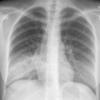

Case 1 Round pneumonia

Date: 04/16/2005

Views: 8001

Round pneumonia